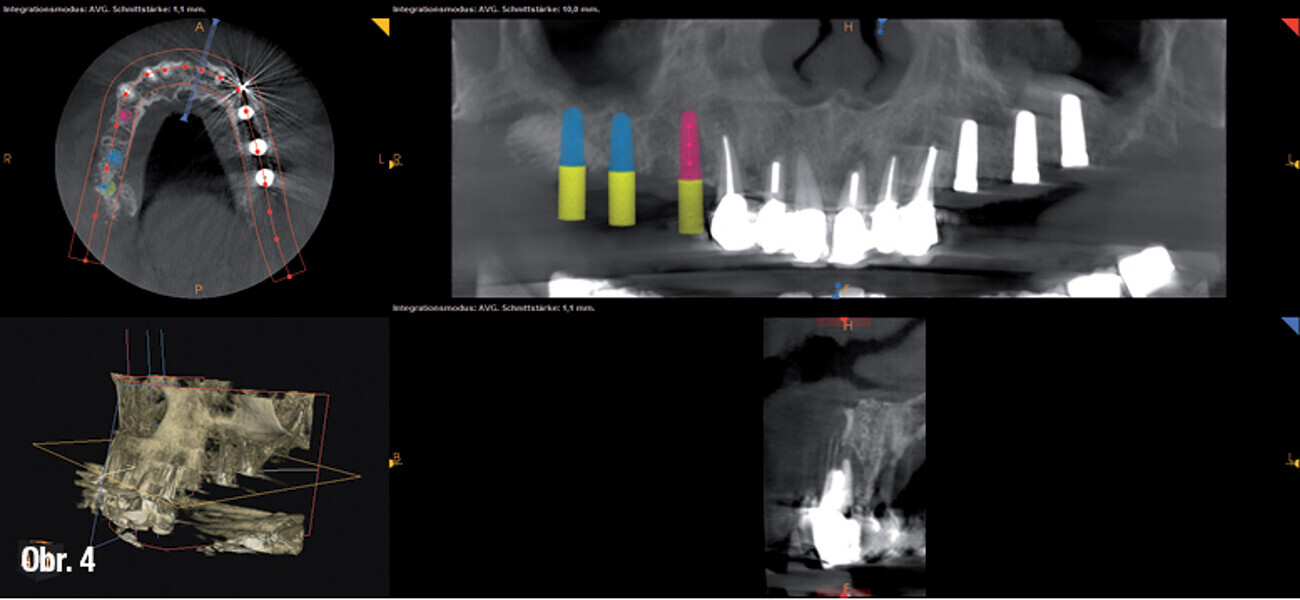

Zubní implantáty – od týmového plánování k esteticky úspěšnému výsledku